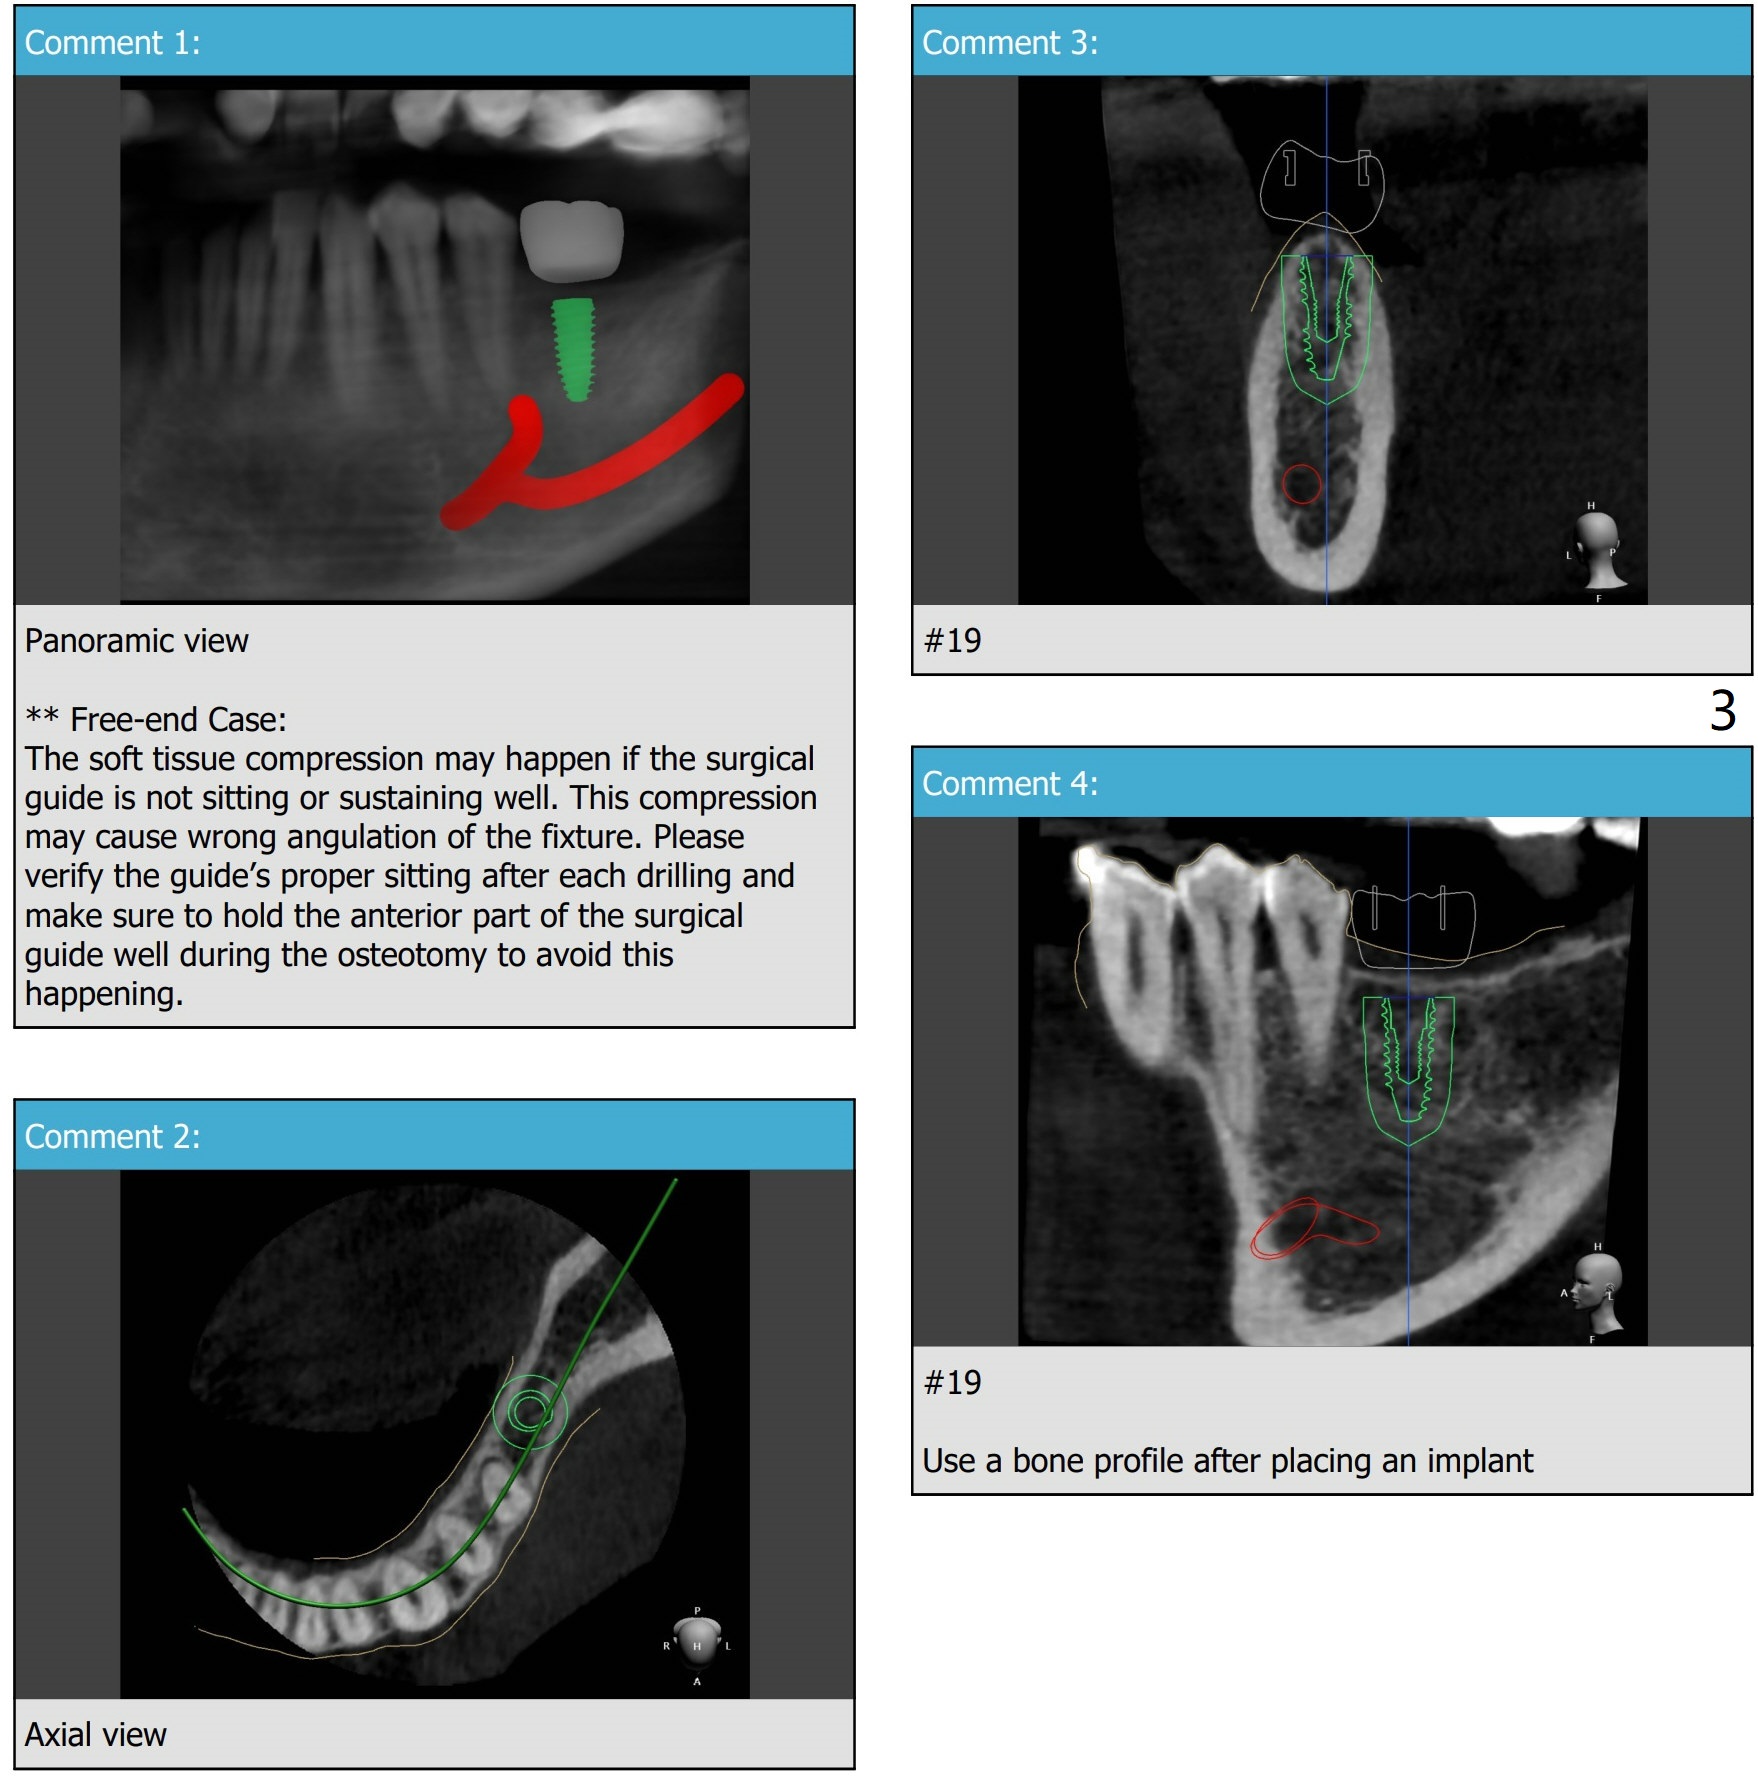

Consider Deviation for Guided Placement of Distal End Implant